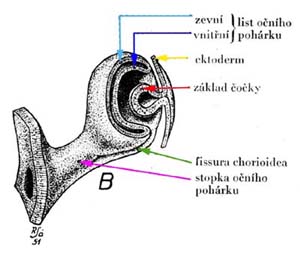

V prvním měsíci embryonálního života vyrůstá z mozkového váčku výběžek - oční váček, který se vchlípením mění na oční pohárek. Z jeho zevního listu pohárku vzniká pigmentový epitel sítnice a z vnitřního listu nervové buňky sítnice i jejich podpůrné buňky.

V 5. týdnu embryonálního života vzniká primitivní terč zrakového nervu a začínají se vytvářet první buňky budoucí sítnice - gangliové buňky a Mullerovy buňky.

Buňky v centrální části sítnice se začínají diferencovat nejdříve a již za týden jejich výběžky dosahují až k terči. Tak vzniká základ makulopapilárního svazku. Během dalších několika dnů se diferencují gangliové buňky v perifernějších oblastech sítnice. Těm, které rostou z temporální strany, překáží v cestě ke zrakovému nervu již vytvořený makulopapilární svazek a musí jej obloukovitě obejít. Vlákna rostoucí z gangliových buněk z nasální strany takovou překážku na cestě nemají a jejich průběh ke zrakovému je přímý. Tímto způsobem během několika dní vzniká vrstva nervových vláken. Její uspořádání nám umožňuje pochopit lokalizaci skotomů zorného pole.